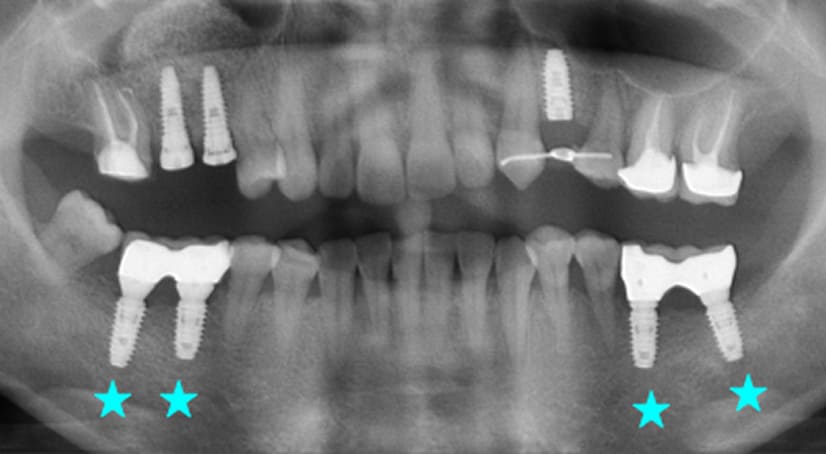

9年以上

-

种植体植入 2012年10月 -

随访:2年 2014年7月 -

随访:9年 2021年9月